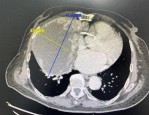

80 岁阿婆胸腔被巨大肿瘤占据,华山医院胸外科医生能否创造奇迹?

巨大的肿瘤几乎占据了80岁阿婆的整个右侧胸腔,最上端几乎延伸近颈部,而最外侧挤压着胸壁,心脏几乎被推至对侧胸腔……并且肿瘤已压迫周围大血管,与无名及上腔静脉(向心脏...